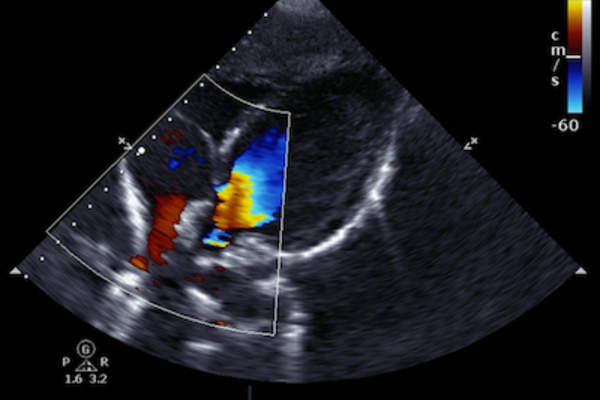

其他的测试也是可能的

这些是用于诊断淋巴瘤最常见的测试。有时,骨扫描,如果病人是有骨痛完成。和超声心动图,multigated采集(MUGA)扫描或肺功能检查往往要求为谁需要化疗,并且可以在用于心脏或肺部疾病风险的患者。